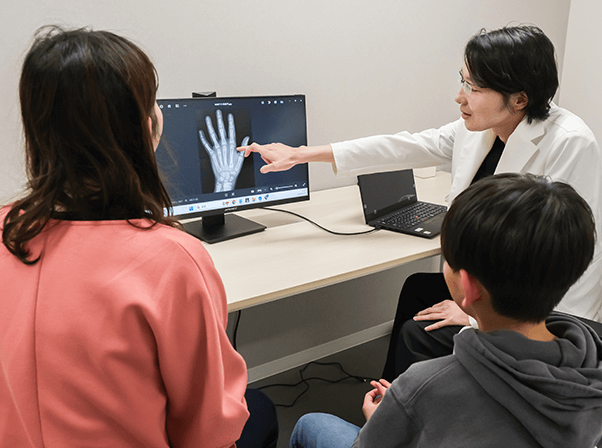

REASON02

当院オリジナル開発

X線検査機器

お子様の成長評価に不可欠な「骨年齢」の測定にはX線検査が必要ですが、体への影響を気にされる保護者の方も少なくありません。

当院では、そうした声にお応えし、医師監修のもと独自に開発した低負担のX線機器を導入。一般的な装置に比べて身体への負担に配慮した設計となっており、安心して検査を受けていただけます。また、撮影は左手のみで行うため、影響を最小限に抑えています。

お子様の健康を第一に考えた、安全かつ高精度な検査体制で、安心して成長評価を受けていただけます。

REASON03 AI成長予測システムを導入

骨の成熟度を評価する「骨年齢判定」は、成長予測や診断において極めて重要な指標です。しかし従来は、医師の目視による判定であるため、評価にばらつきが生じる可能性がありました。

当院では、より高精度かつ客観的な診断を実現するため、世界中の医療現場で導入が進むAI骨年齢解析システムを採用。AIが骨の形状や成長状態を数値化し、数分で信頼性の高い骨年齢を自動解析します。

医師の専門的な判断にAIのデータを掛け合わせることで、より的確な成長評価・治療計画が可能となります。